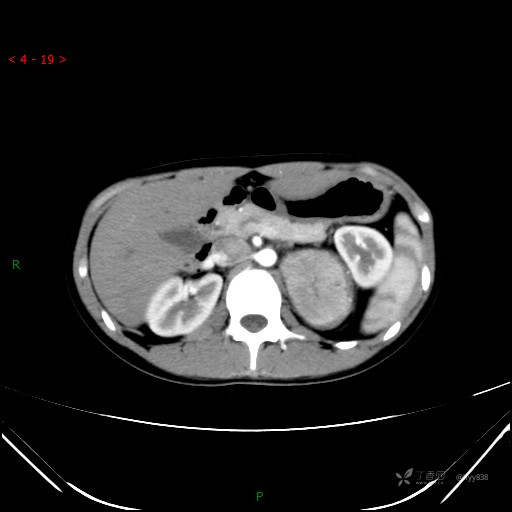

增强动脉期